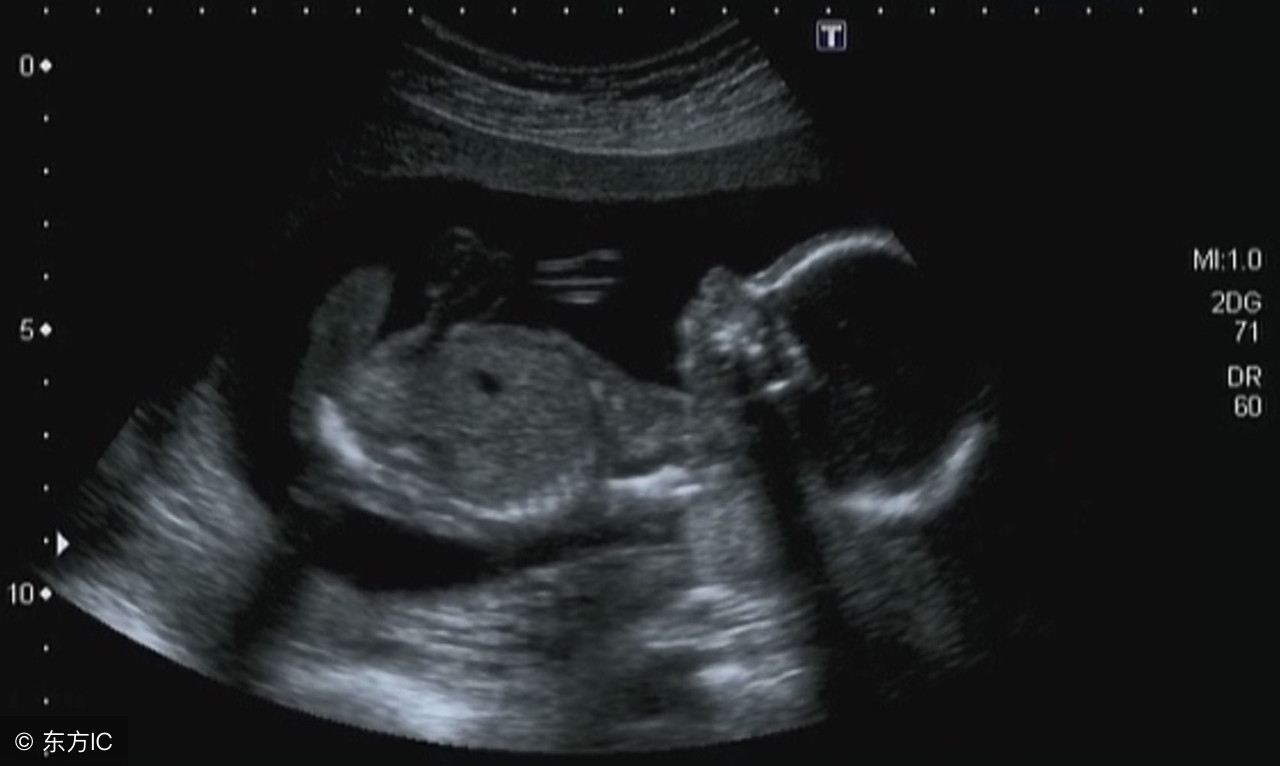

妊娠是一个复杂的过程,卵子受精后,进入宫腔,胚胎及附属物迅速生长发育直至成熟的过程中,每个孕周都会有不同的变化。每次我们去医院B超单上各组数据就是看不懂,问医生也不可能什么都问到,这篇文章帮你看懂自己的B超单!

8周:胎儿长到1.66厘米,胎形已定,可分出胎头、体及四肢,胎头大于躯干。B超可见胎囊约占官腔1/2,胎儿形态及胎动清楚可见,并可看见卵黄囊。

9周:胎儿长到2.15厘米,胎儿头大于胎体,各部表现更清晰,头颅开始钙化、胎盘开始发育。B超可见胎囊几乎占满宫腔,胎儿轮廓更清晰,胎盘开始出现。

10周:胎儿长到2.83厘米,胎儿各器官均已形成,胎盘雏形形成。B超可见胎囊开始消失,月芽形胎盘可见,胎儿活跃在羊水中 。

11周:胎儿长到3.62厘米,胎儿各器官进一步发育,胎盘发育。B超可见胎囊完全消失,胎盘清晰可见。

12周:胎儿长到4.58厘米,外生殖器初步发育,如有畸形可以表现,头颅钙化更趋完善。颅骨光环清楚,可测双顶径,明显的畸形可以诊断,此后各脏器趋向完善。